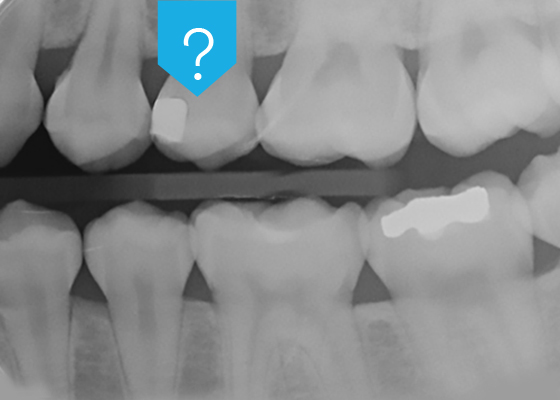

Even if natural hard dental substances do not contain highly radiopaque chemical elements, they still offer a certain degree of radiopacity. This is due to the calcium and phosphorus in their inorganic component, the hydroxylapatite. These elements are more concentrated in enamel than in dentin, making enamel more radiopaque than dentin. During the caries process, bacteria-produced acids cause hydroxylapatite to be released from the dental tissues, which is why carious lesions appear less radiopaque than intact enamel or dentin.

As esthetic restorations are increasingly bonded to the tooth with the help of universal adhesive systems, an important problem has remained unresolved: universal adhesives are radiolucent.

A radiolucent adhesive makes it impossible to differentiate between adhesive pooling and secondary caries, marginal gaps or voids beneath the restoration, particularly in difficult-to-inspect areas. Very experienced practitioners may try to distinguish between secondary caries and the adhesive layers by taking the morphology of the radiolucency into consideration, but it remains an educated guess with no guarantee. To be 100% sure, and to avoid legal problems, many practitioners prefer to replace the restoration entirely, which may end up being completely unnecessary. In these cases, radiopacity is clearly a desirable property for dental adhesives.

This new universal adhesive’s radiopacity is comparable to that of sound, non-demineralized dentin.2 It is also in line with ISO 4049, which specifies that the radiopacity of restorative materials should be at least as high as the radiopacity of aluminum of the same thickness.3 This makes it possible to make a clear distinction between secondary caries, marginal gaps or voids and the adhesive layer in a clinical setting.